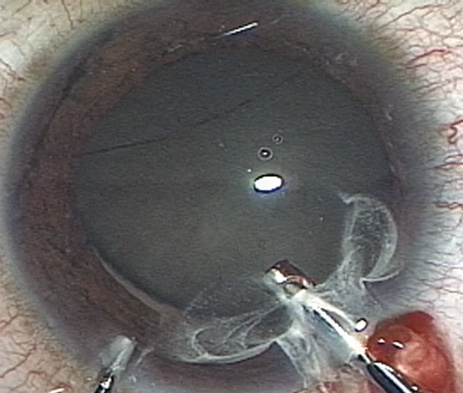

Many patients are most bothered by cataract-induced glare. For these patients, acuity testing under glare situations is indicated. There are several methods to assess visual acuity reduction by glare. The choice of method is often best dictated by the patient's history. If a patient complains of glare problems in the supermarket, or other uniformly illuminated environment, the brightness acuity test can be performed (Mentor Ophthalmics). For this test, the specially illuminated handpiece is held in front of the tested eye using best spectacle correction (Fig. 1). The Snellen acuity is rechecked and can be recorded on each of three light settings.

Patients who complain of glare from point sources of light, such as oncoming headlights or bright sunshine, may be best evaluated by a different form of glare testing. To simulate the environment of the patients' symptoms, Snellen acuity is measured while directing a point source of light obliquely toward the eye outside their best spectacle correction or outside of a phoropter dialed in with their best manifest refraction (Fig. 2).